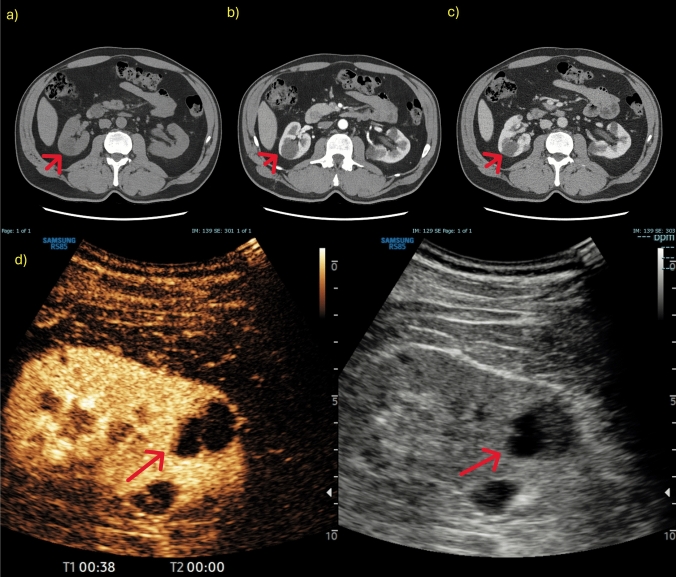

对比增强超声(CEUS)已成为检测和表征实性肾脏病变的重要工具,补充了传统的b型超声,后者往往难以区分实性和囊性肿块。超声造影通过提供详细的血管化信息来提高诊断的准确性,有助于识别潜在的恶性实体病变,并区分假肿瘤和实体肿块。此外,超声造影使用的造影剂即使对肾病患者也是安全的,并且可以不考虑肾功能,使其成为肾脏成像的有利方法。在这篇叙述性综述中,根据欧洲超声医学和生物学协会联合会的指南,作者展示了其主要适应症:在移植肾患者中诊断不确定的肾脏病变,监测非手术病变,诊断炎症-感染性肾脏病变,评估手术床上的晚期肾脏病变和肿块。

Contrast-enhanced ultrasound (CEUS) has become an important tool for the detection and characterization of solid renal lesions, complementing traditional B-mode US, which often struggles to distinguish between solid and cystic masses. CEUS enhances diagnostic accuracy by providing detailed vascularization information, helping to identify potentially malignant solid lesions and differentiate between pseudotumours and solid masses. Moreover, CEUS employs a contrast agent that is safe even for nephropathic patients and can be used without concern for kidney function, making it an advantageous method for renal imaging. In this narrative review, following the European Federation of Societies for Ultrasound in Medicine and Biology guidelines, the authors show its main indications: characterizing indeterminate renal lesions in patients with transplanted kidney, monitoring non-surgical lesions, diagnosing inflammatory-infectious renal pathologies, and assessing advanced renal lesions and masses in the surgical bed.